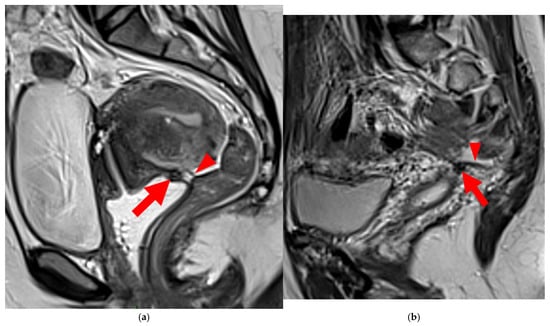

Figure 12. Pelvic MRI scan of a patient with a HTD type 6 left USL. (a,b) Axial (a) and sagittal (b) T2WI show a spiculated nodular hypointense lesion (arrowheads) extensively involving the left inferior hypogastric plexus contained within the sacro-recto-genital septum, as well as its afferent and efferent nerve fibers.

Figure 13. Pelvic MRI scan of a patient with a HTD type 6 right USL. (a,b) Axial (a) and sagittal (b) T2WI show a spiculated nodular hypointense lesion (arrows) located in the right cardinal ligament (a.k.a. Mackenrodt ligament), affecting the uterovaginal nerve plexus, a component of the inferior hypogastric plexus. Note the steep vertical orientation of the right proximal USL (arrowhead), which is reclassified from type 3B to type 6 due to this so-called “visceral” involvement.

A type 6 USL is associated with adjacent pelvic “visceral” involvement in a broad sense. It most commonly affects the digestive tract (Figure 8 and Figure 9), with the rectum and rectosigmoid junction wall thickening: in this case, the lesion often appears as a “medallion-shaped” protrusion into the lumen. Less frequently, the urinary tract is affected (Figure 9 and Figure 10), involving the muscular layer of the bladder or even the distal ureter at the level of the common iliac artery, with stenosis potentially leading to upstream hydronephrosis. More rarely, as USLs are also close to nearby pelvic nerve structures (Figure 11), contiguous involvement of the inferior hypogastric plexus located in the sacro-recto-genital septum (a.k.a. Delbet sagittal fascia) beneath the distal two-thirds of the USL, or exceptional involvement of the sciatic nerve adjacent to the pelvic wall, is possible (Figure 12, Figure 13 and Figure 14).